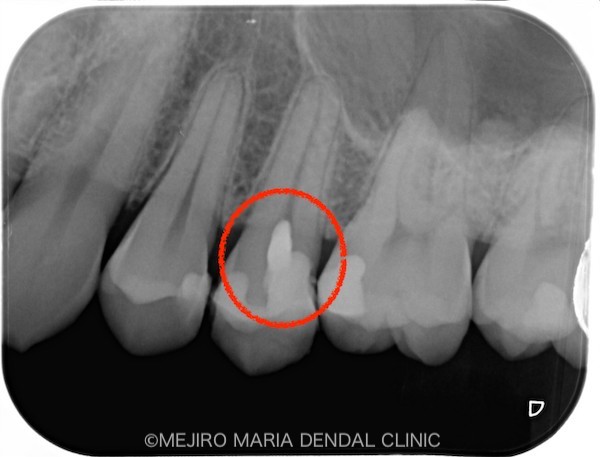

前医で充填された歯科用素材を除去後(写真1)、さらに虫歯が確認できて、容易に露髄(神経に到達すること)しました。

洗浄液と適切な止血によって、歯髄からの出血をコントロールできた(写真2)ことから、炎症組織は取りきれたと判断し、当日に予定どおり「生活歯髄保存療法」を行い、経過を確認していくこととしました。